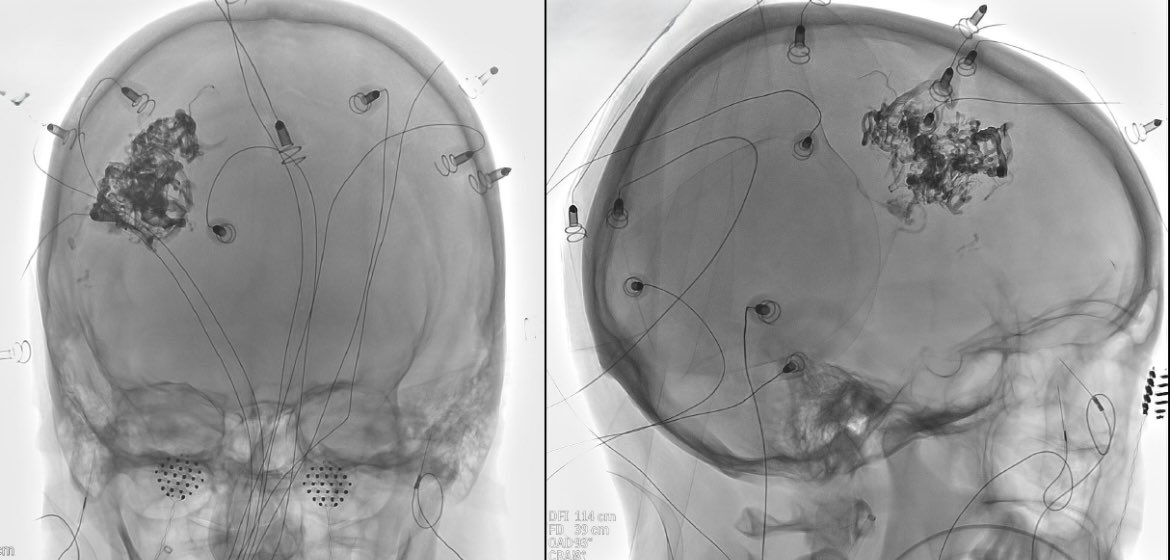

Ruptured cerebral arteriovenous malformation (#AVM), S&M grade IV

#Embolization + #Surgery

Complete Removal !!

Great team !!

Dr. Alberto Blanco (NSG)

Dr. Raquel Alcaraz (AN)

Dr. Raquel Tolos (AN)

Dr. Nerea Joshua (Neurophysiol)

@Sremollo

@IsaRCaamano

Rosa García-Sort (INR Nurse)